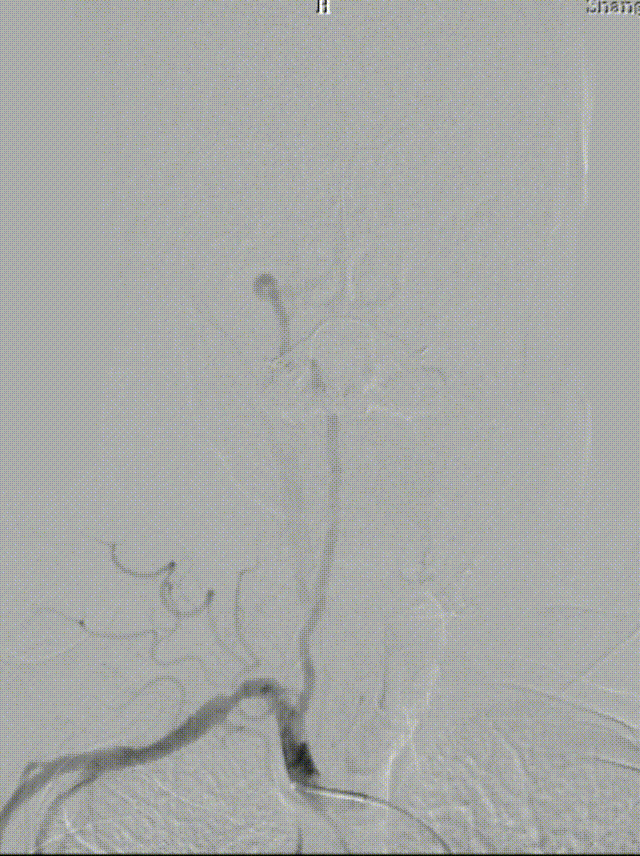

造影见LV闭塞,立即沿0.014*200cm 通桥北斗SS™神经血管导丝置入3mm*16mm 药物球扩支架至LV1。

压力泵逐渐加压球扩支架到8atm, 支架打开良好,造影示残余狭窄0%。

双侧锁骨下动脉造影见椎动脉、基底动脉血流通畅,远端未见栓塞表现。

通桥北斗SS™神经血管导丝操控性优异,术中表现出优良的穿越狭窄病变以及携带支架能力。

左椎支架开口下端斑块完全覆盖,减少远期再脱落风险。

术中即刻发现出现栓子脱落左椎动脉闭塞,立即予替罗非班负荷量并置入支架。后续复查左侧小脑虽有梗死病灶,但患者神经功能无缺损,头晕症状完全消失,下肢拖曳也完全消失,生活完全恢复至正常。